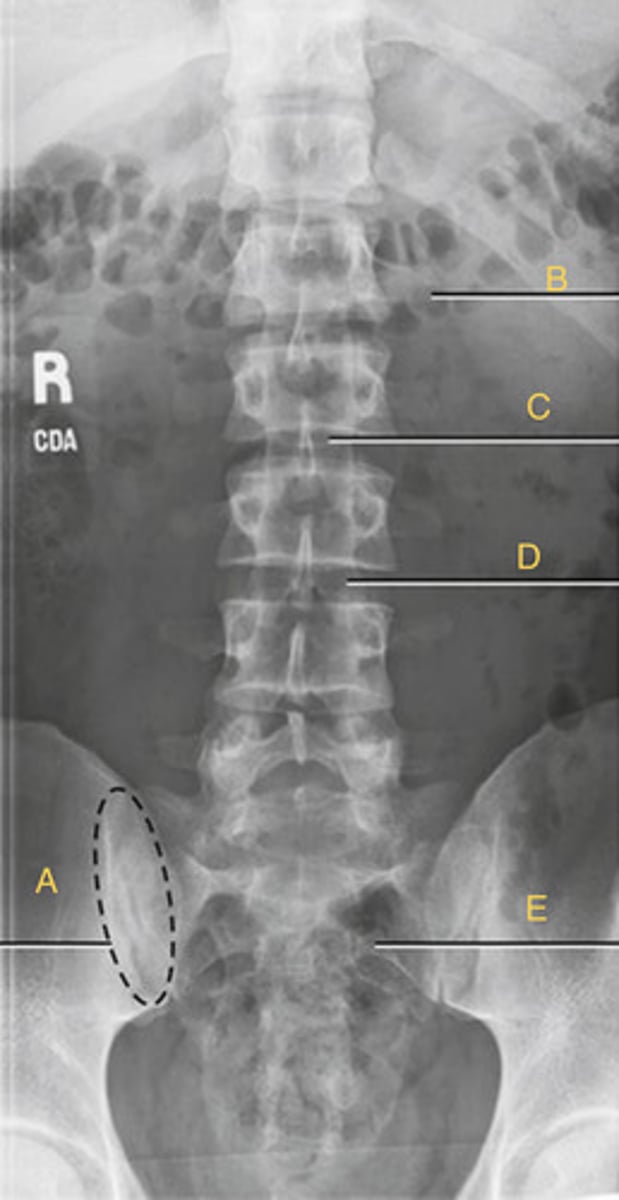

R sacroiliac joint

A.

L1 transverse process

B.

L2 spinous process

C.

L3-4 intervertebral space

D.

Ala of sacrum

E.

AP L spine

What position?